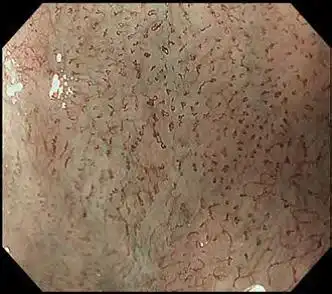

光学85X放大倍数

该范围放大图像85x*2,其高清图像质量轻松提供粘膜表面的视图。结合更明亮的NBI(窄带成像),粘膜组织和毛细血管网络得到增强,进一步支持详细观察。

白光 用NBI光学放大85x